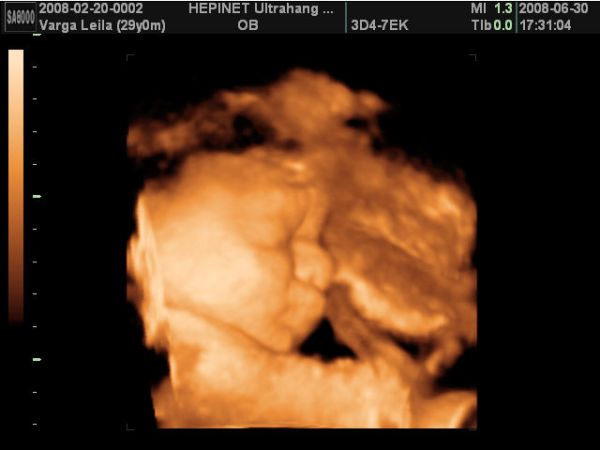

Azért,ha nem baj, mutatok két képet a kisfiamról a pocimban. A képek múlt héten készültek 4D-n:

Kép Csabi

Kép Csabi2